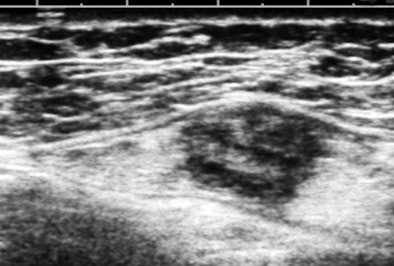

The image above is a breast cancer not suspected in screening mammography or physical exam in a woman referred for chest-wall pain (on the opposite side of the body). This lesion was found incidentally while scanning the upper outer quadrant of the left breast. The way we examine the breast is to think of the breast as a clock face with the nipple at the center, use a high-frequency array, orient the transducer perpendicular to a zone like a 2 o'clock radian, and slide the transducer from the nipple outward.

This suspicious nodule was immediately evident during continuous viewing. We decided to look at the breasts, because the patient had traveled some distance to get to us from a rural area with limited diagnostic resources and because she had expressed some anxiety about breast cancer.

Being able to see the image in real-time is one of the most powerful aspects of ultrasound. It makes it easy to adjust the settings while you are looking at the image, and, of course, to optimize probe position. However, the fact that contrast sensitivity is so much better for moving pictures than for still ones is what really elevates ultrasound as a diagnostic imaging technique. In essence, dynamic viewing increases the signal-to-noise features for lesion detection; it's especially valuable when noise is high, such as when scanning through a lot of subcutaneous fat or with equipment that does not have speckle reduction.